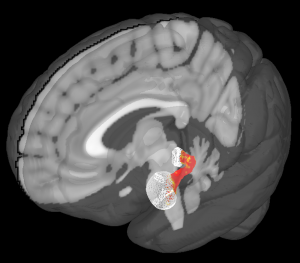

Altruists have stronger-than-average structural connections between the amygdala and periaqueductal gray, the parts of the brain shown here. Katherine O’Connell, CC BY-SA

What we found suggests that these two regions might be communicating or otherwise working together. We further tested this finding by looking at another aspect of our brain scans that allowed us to analyze how these two regions are connected by nerve cells.

My colleague Katherine O’Connell, a doctoral student, found that there seemed to be greater structural connections between these two regions too. These connections may help nerve impulses travel between them.